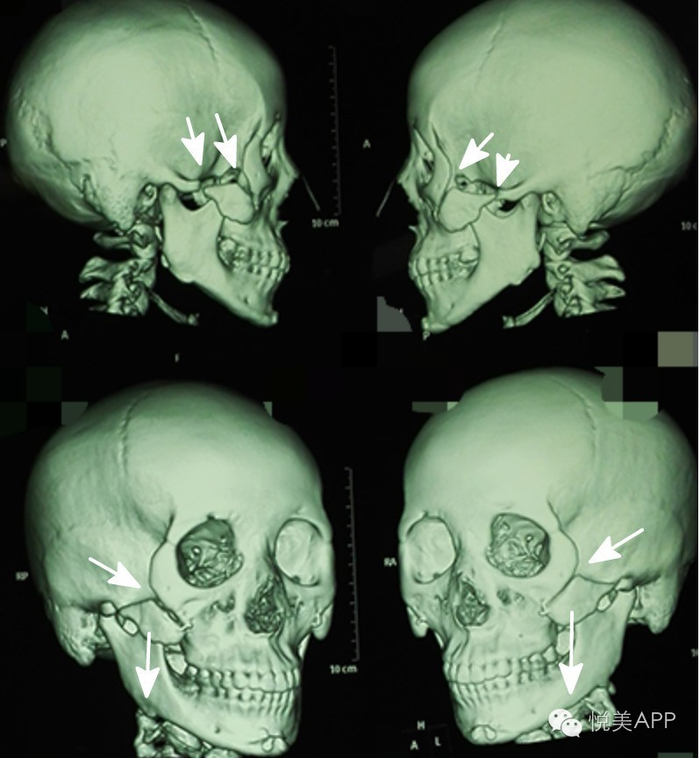

颧骨颧弓内推的极限是多少?

颧骨内推是有一定限度的,颧弓内推的极限决定于颧弓和下颌骨喙突之间的距离,颧弓内推只要不妨碍下颌骨喙突的运动,可以达到极限值。

下颌骨喙突位置:

也就是白色圆圈内的两块骨头距离,推太多会导致张口受限,影响功能

下面是不固定引发的悲剧:

比如A去韩国做了颧骨下颌角,前端只用两个小钢丝固定,后端居然不固定。才两个月,颧骨体已经掉下来,后方截骨线完全不连,前方右侧截骨线不连,最后找到国内最负盛名的专家之一修复。

修复后

但咬肌的强大力量长期牵引,仍然造成了以下案例后端骨端的下滑,同时对前方的颧骨固定点形成了杠杆作用,强大的杠杆力使得前方固定点上端裂开。最终使颧弓向后下方旋转,翻转。

以下案例,后端未固定,只把整段骨块内移插入到后方骨端的内侧,但由于术后患者的咬肌运动,牵拉骨块,使得后段本来重叠推进去的骨端弹出,所以面部宽度最终未能缩小。

骨不连,骨块下移

颧弓根部的截骨少量内推时,内推范围不超过颧弓根截面,要能接上才能骨性愈合。推多了后端骨头连不上,仅靠钛板固定,在咬肌牵拉下,单靠钛板钛钉固定仍然容易骨不连、下移、弹出。

后端的牵拉对前端造成杠杆效应,使得前方固定点上端裂开,最终使颧弓向后下方旋转,翻转。导致骨不连,骨块下移。